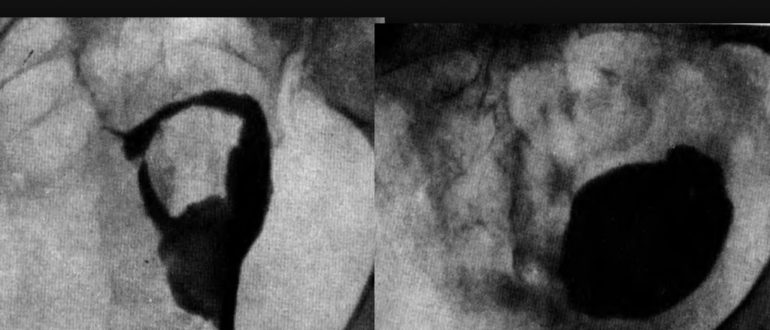

Что означает лт-эм с маточными трубами

3 признака непроходимости маточных труб: лечение, симптомы и осложнения Сегодня по медицинской статистике непроходимость маточных труб у женщин — сокращенно НМТ — самое распространенное гинекологическое заболевание и одна из частых причин женского бесплодия. Именно…